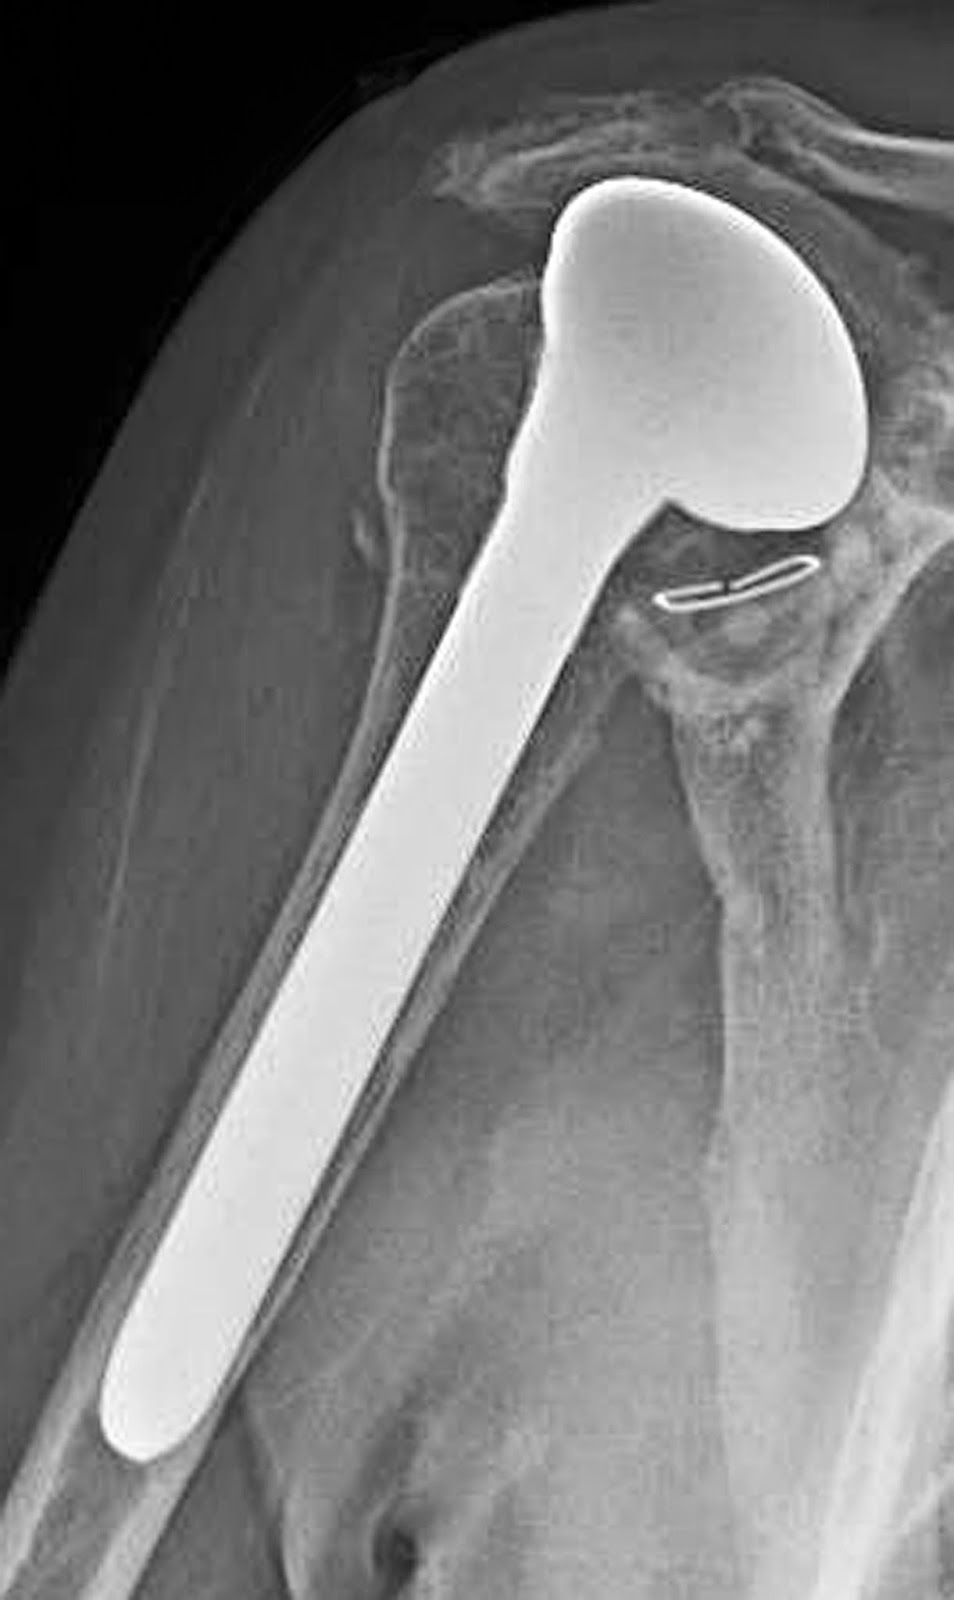

UW Shoulder and Elbow Academy Rotator cuff tear arthropathy and the Rotator Cuff Tear Misdiagnosed As Frozen Shoulder Both frozen shoulder and rotator cuff tears are common shoulder injuries that can cause pain and limit. people who've had to keep a shoulder somewhat still are at higher risk of developing frozen shoulder. shoulder pain and stiffness, arm weakness, and limited range of motion are symptoms that can occur with a rotator cuff tear as. rotator. Rotator Cuff Tear Misdiagnosed As Frozen Shoulder.